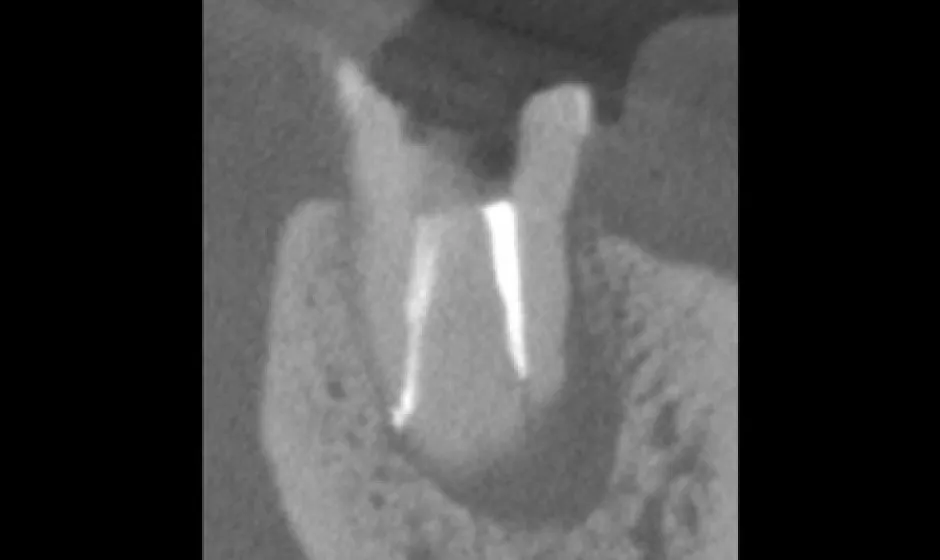

01精密根管治療

「抜くしかない」と言われた歯でも、根の中の感染を適切に抑えられる治療技術があれば、歯を残せる可能性があります。根管は非常に細く複雑で、わずかな取り残しが痛みや腫れの再発につながることもあるため、当院では必要に応じてCTやマイクロスコープを活用し、原因を見極めながら丁寧に処置を進めます。

医療法人大杉歯科医院が大切にしているのは、早く終える治療ではなく、歯を守る治療。津市で、できるだけ天然歯を残したい方の選択肢になれるよう取り組んでいます。症例1

- 治療名

- マイクロスコープとラバーダムを使用した精密根管治療

- 患者様

- 30代男性

- 執刀医

- Dr. 大杉

- 治療期間

- 3ヶ月

- 治療費

- 精密根管治療:130,000円(税込)

築造:40,000円(税込) - リスク

- 治療中〜治療後に痛みが出る場合あり

再感染・治癒不全の可能性

補綴後も定期管理が必要